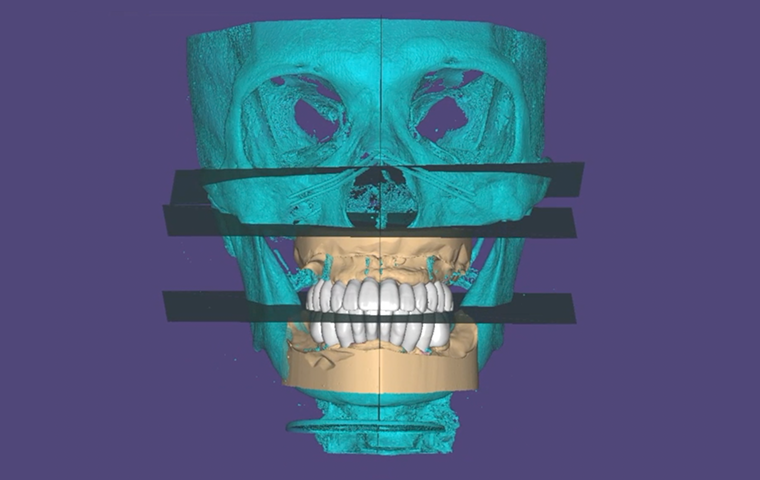

All-on-X

Practical Digital Prosthodontics: Understanding and applying

All-on-X treatment concept

Dr. Janghyun Paek

Professor at Kyunghee University, Department of Prosthodontics

All-on-X

Practical Digital Prosthodontics: Understanding and applying

All-on-X treatment concept

Dr. Janghyun Paek

Professor at Kyunghee University, Department of Prosthodontics

| 13:30 – 14:30 |

All-on-X

Dr. Janghyun Paek

|

Practical Digital Prosthodontics: Understanding and Applying All-on-X Treatment Concept |

| 13:30 – 14:30 |

All-on-X

Dr. Janghyun Paek

|

Practical Digital Prosthodontics: Understanding and Applying All-on-X Treatment Concept |

Special Pre-Day Course

Practical Digital Minimalism

Dr. Janghyun Paek

Explore the digital implant dentistry, including the All-on-X treatment concept, guide surgery, immediate loading protocols, prosthodontic considerations, and soft tissue contouring. Course also includes hands-on for All-on-X implant placement, prosthodontic components, intraoral scan, and immediate loading.

Explore the digital implant dentistry, including the All-on-X treatment concept, guide surgery, immediate loading protocols, prosthodontic considerations, and soft tissue contouring. Course also includes hands-on for All-on-X implant placement, prosthodontic components, intraoral scan, and immediate loading.